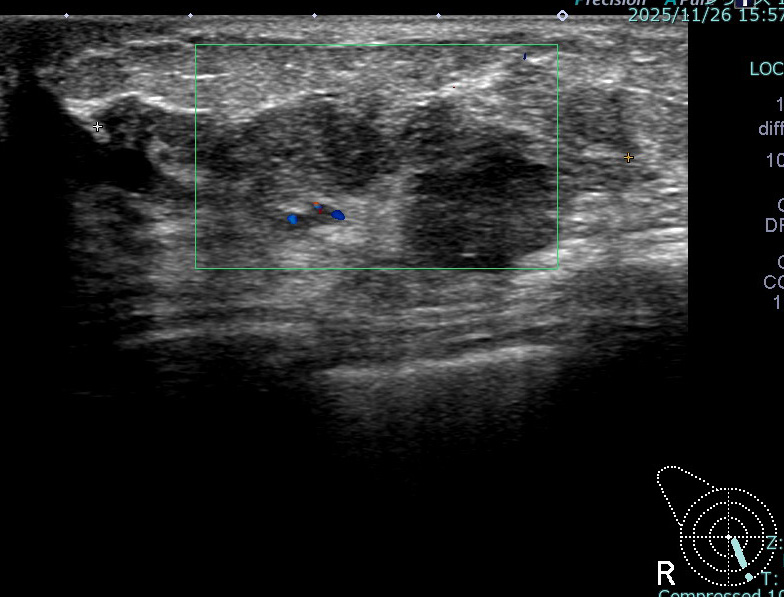

このエコー像だと乳頭(画面左上)から乳管内を増殖(画面右方向へ)しているように見える

腫瘤形成していても、乳管内で広がることで浸潤していない場合もある

術前エコー(1か月前)